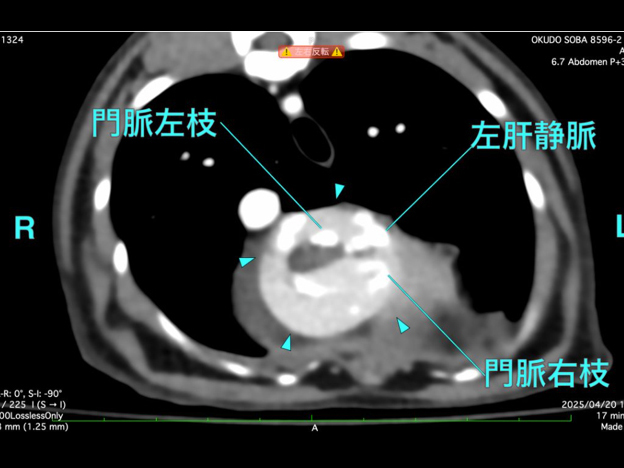

詳しく調べるためにCT検査を行った結果、「腹膜心膜横隔膜ヘルニア」と診断されました。

CT検査にて手術前評価